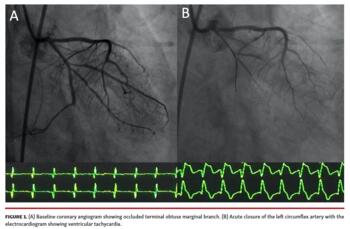

A 45-year-old man presented with complaints of chest pain for 6 hours. Electrocardiogram was suggestive of inferior wall ST-segment elevation myocardial infarction (STEMI). The patient did not approve primary percutaneous coronary intervention (PCI) and was thrombolyzed with tenecteplase. However, there was no relief in chest pain and the patient developed cardiogenic shock. He was taken for rescue PCI. Left coronary angiogram showed complete thrombotic occlusion of the terminal obtuse marginal branch (Figure 1A; Video 1). The left circumflex artery was crossed with Runthrough extra floppy NS guidewire (Terumo). The patient developed worsening ST elevation and ventricular tachycardia, which was cardioverted by giving 2 shocks of 200 J. Left coronary angiogram showed occlusion of the left circumflex artery (LCX), right from the ostia (Figure 1B; Video 2). We initially thought of thrombus migration as the cause of acute vessel closure. Initially, dottering and subsequent dilation of the left circumflex was done with a 2.0 x 10 mm semicompliant balloon. The activated clotting time was 356 seconds. There was not much improvement in the blood flow in the LCX. We suspected coronary spasm and gave multiple 50 µg boluses of intracoronary nitroglycerin. Subsequently, brisk flow was established in the LCX (Figure 2; Video 3). The lesion was stented with a 2.75 x 18 mm everolimus-eluting stent. ST-segment changes settled after the PCI.